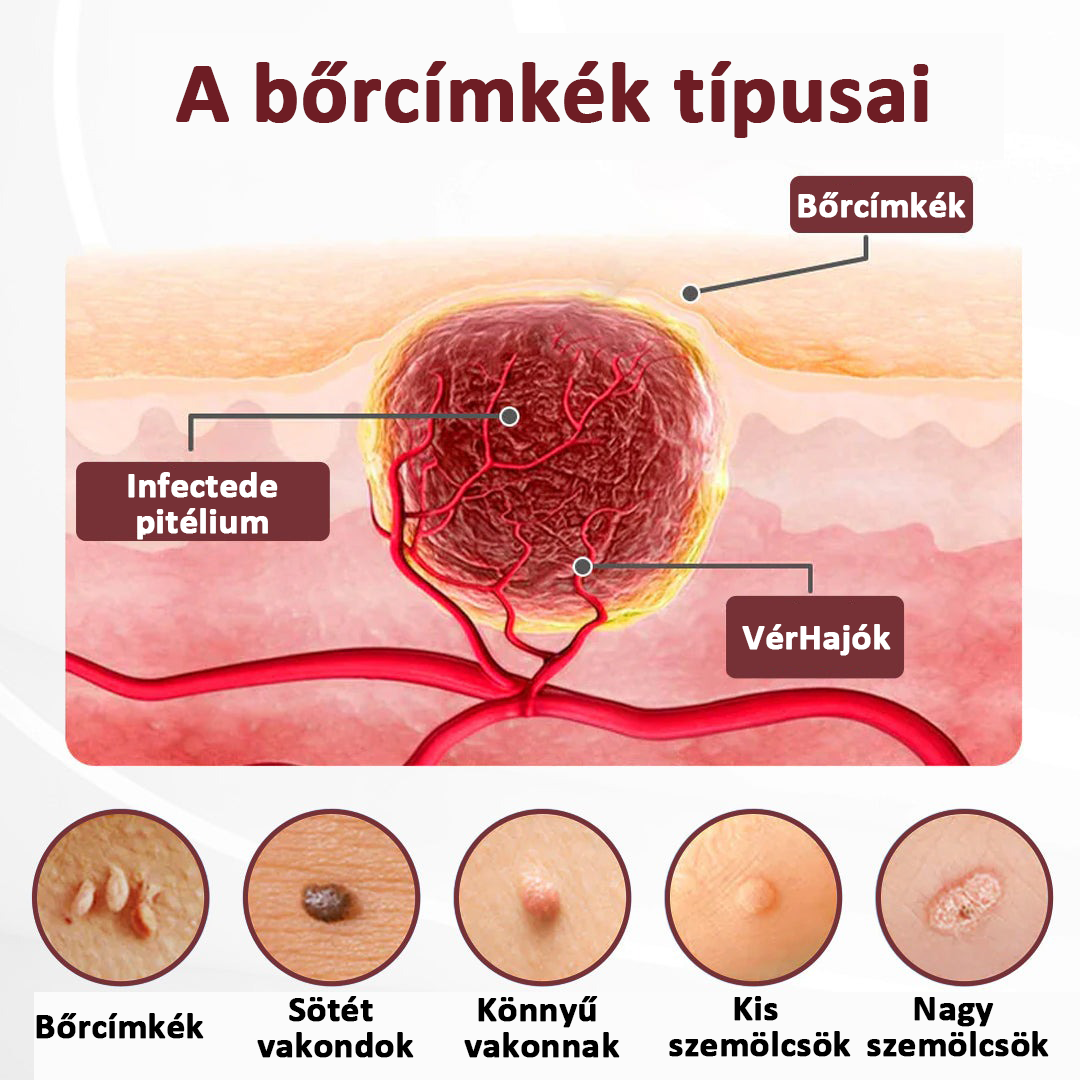

Bőrkinövések, szemölcsök, apró dudorok és érdes foltok gyakran akkor alakulnak ki, amikor a bőr a következő tüneteket tapasztalja:

Bőrkinövések, szemölcsök, apró dudorok és érdes foltok gyakran akkor alakulnak ki, amikor a bőr a következő tüneteket tapasztalja:

• Mély keratinlerakódás

• Enyhe bőrvastagodás súrlódás miatt

• Krónikus szárazság és irritáció

• A kollagéntermelés lassulása az életkorral

• Pigmentlerakódás a sérült szövetek körül

Ezek a változások kiemelkedő, érdes, sötétebb területeket hoznak létre – különösen a nyakon, a hónaljban, a mellkason, az arcon és a test redőiben.

Látható javulás tapasztalható a következők miatt:

✔ A megkeményedett keratin feloldódik

✔ A kiemelkedő dudorok ellaposodnak

✔ A pigmentfoltok halványulnak

✔ Visszaáll a normál bőrtextúra

A legtöbb pattanás- és szemölcskezelés azért kudarcot vall, mert csak a felszínen hatnak. A savak égetik, a hámlasztás irritálja a bőrt, a vény nélkül kapható bőreltávolítók csak a felső réteget emelik fel, a hidratálók pedig nem tudják feloldani a megkeményedett keratint – így a pattanások visszatérnek.

A KeraErase másképp működik: puhítja a pattanásokat, feloldja a mélyen lévő keratint, világosítja a sötét foltokat és simítja a bőr textúráját – mindezt égés vagy irritáció nélkül.